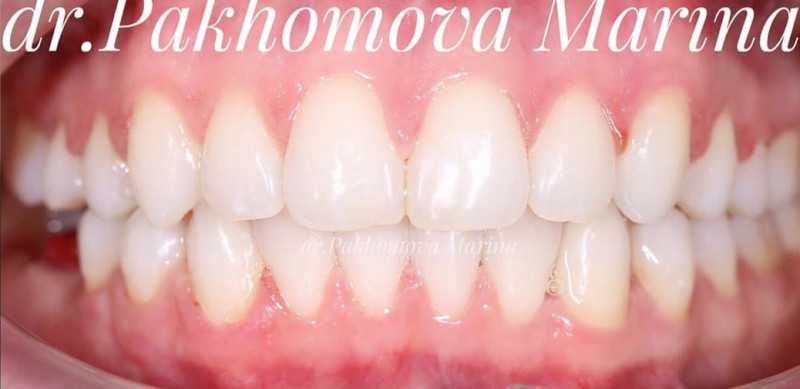

1 работа в портфолио

О стоматологе